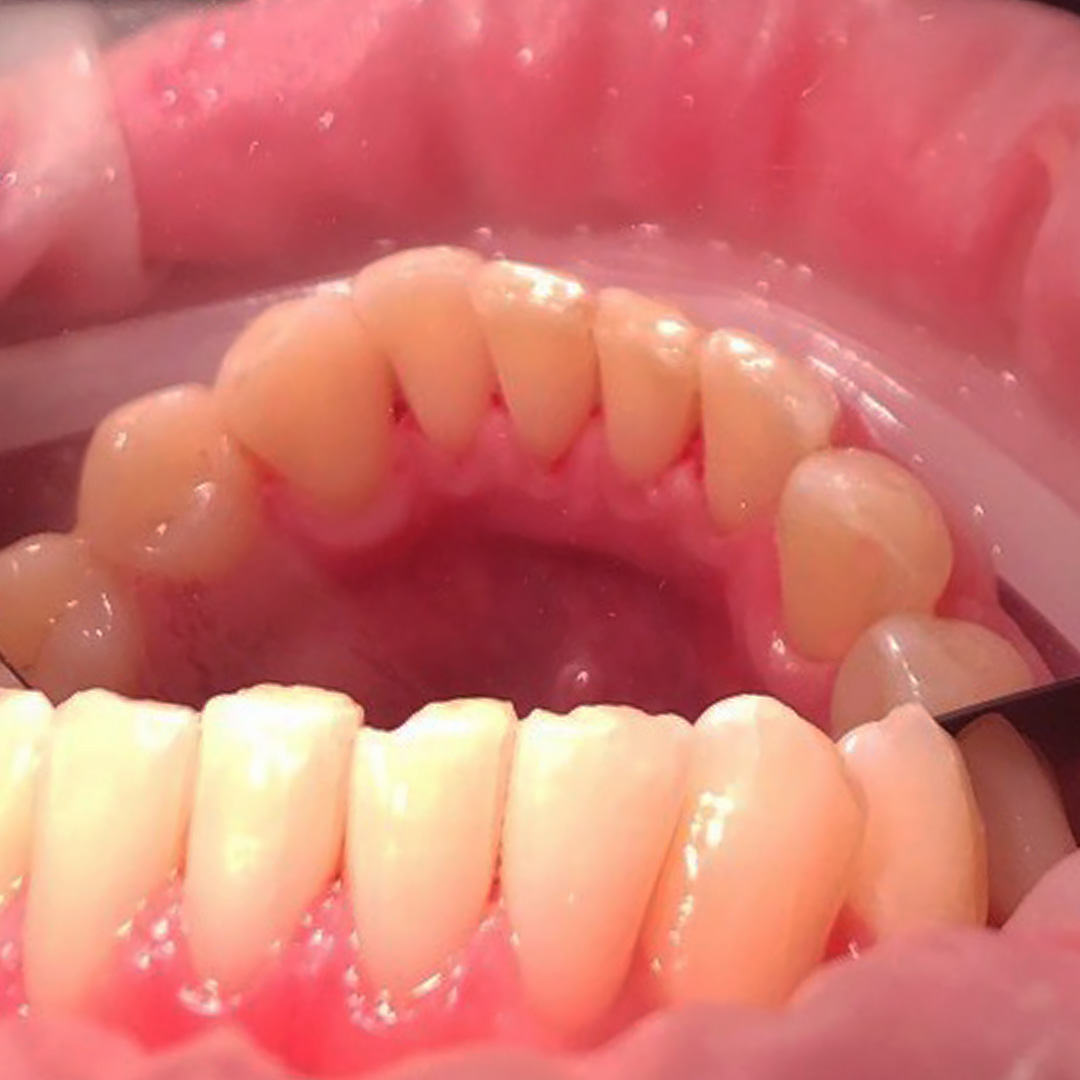

До и после лечения

Пациент обратился с жалобой на наличие зубных отложений и кровоточивость во время чистки зубов. Во время осмотра были выявлена над- и поддесневые отложения. Маргинальная десна отечна и гипермирована, при зондировании кровоточит.

Ход лечения:

- удаление над- и поддесневых отложений с помощью УЗ-аппарата

- профессиональная чистка зубов пастой Detarine Z